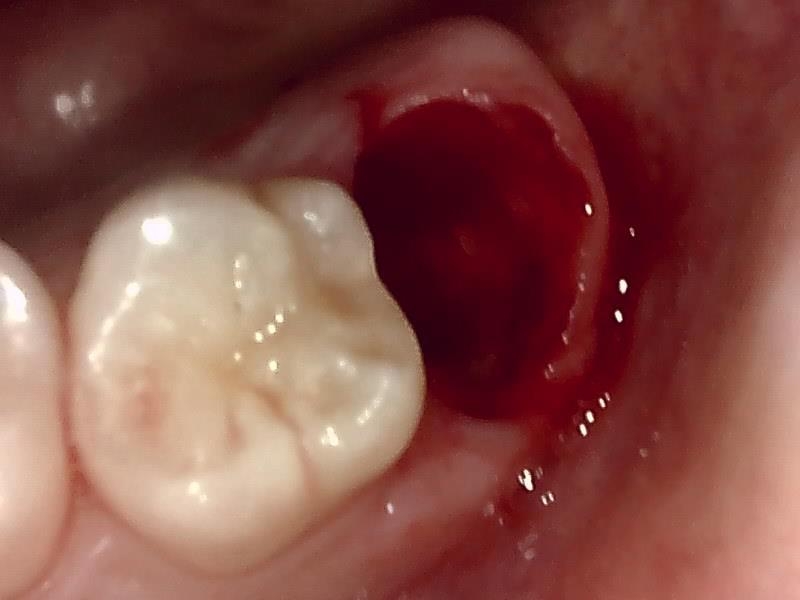

抜歯窩

縫合

右上8番智歯

抜去歯

歯肉を切開し、歯が見えるようにして、

周辺の骨を削らないように親知らずを分割し抜きやすくしていきます。

この抜歯法により術後の腫れ痛みが大幅に軽減されます。

傷口は最小限に、骨は極力削らずに行います。

骨が歯を覆っているケース以外は骨を削ることはありません。

親知らずのみにアプローチし歯を分割し最小限の傷口で取り出します。